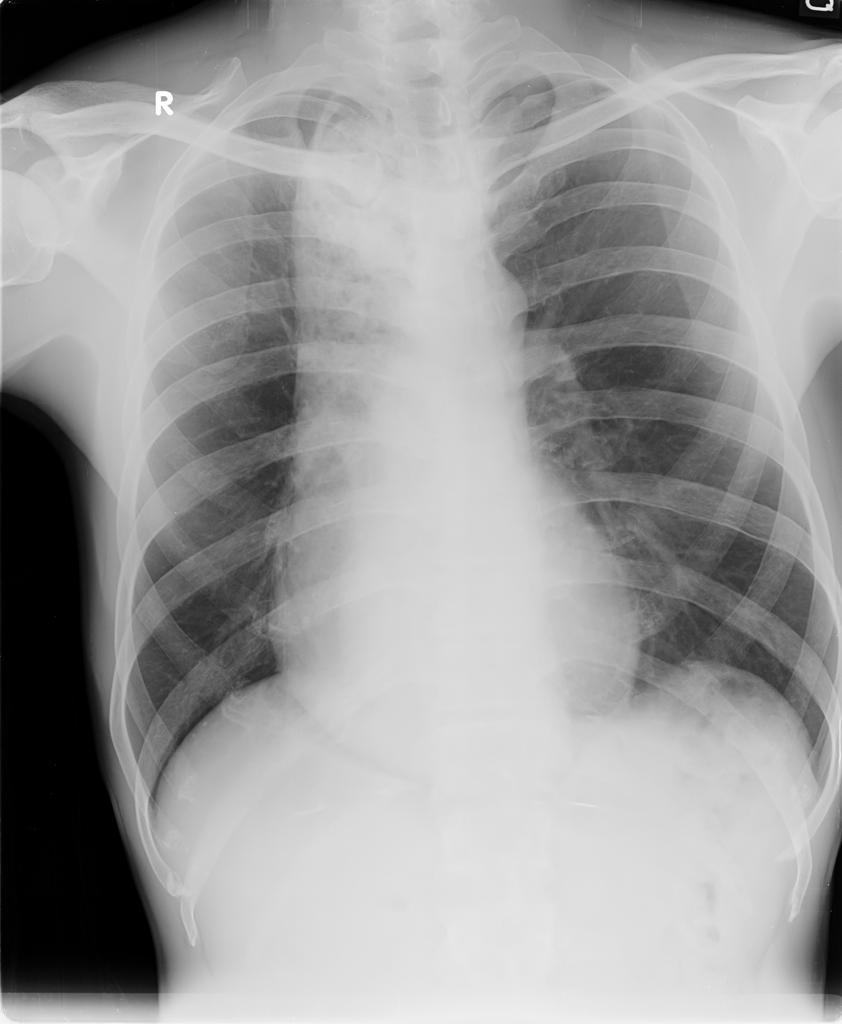

Double heart border, dysphagia

Expanded oesophagus in achalasia

May also show air or fluid level behind the heart